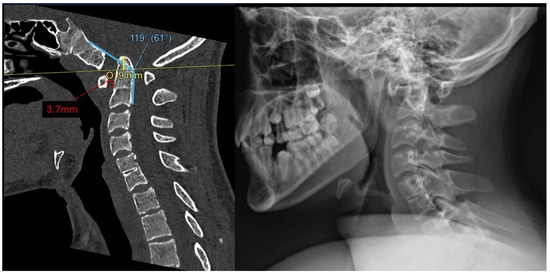

2.2. Imaging and Diagnosis

3.1. Preoperative Planning and 3DPI Design